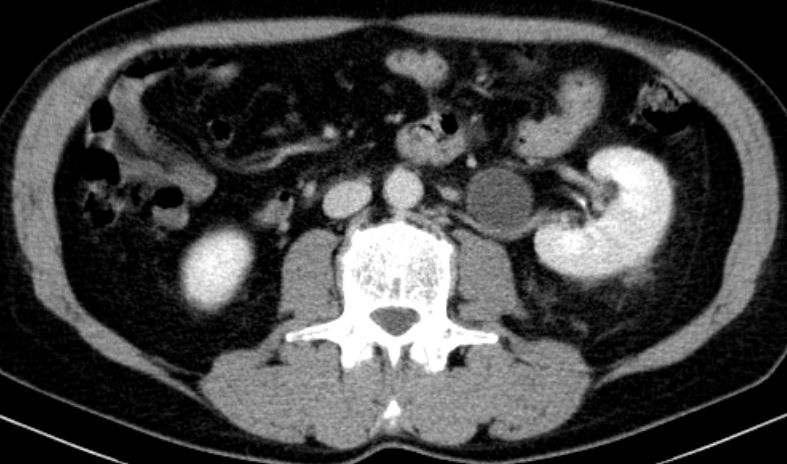

Entdifferenziertes Urothelkarzinom des rechten proximalen Harnleiters pT4 G3 L1

Nierenbecken-Karzinom in einer Doppelniere

Doppelniere links. Im oberen Anteil Hydroureter und Hydropyelons mit Wucherungen eines schlecht differenzierten Urothelkarzinoms mit Plattenepithelmetaplasie, infiltriert das umgebende Fettgewebe.G3. pT3, pN3 (2/3, 1 Lymphknoten mehr als 5 cm) L1. V0. Das CT zeigt den Nierenbeckentumor und eine Lymphknotenmetastase medial des erweiterten Ureters.